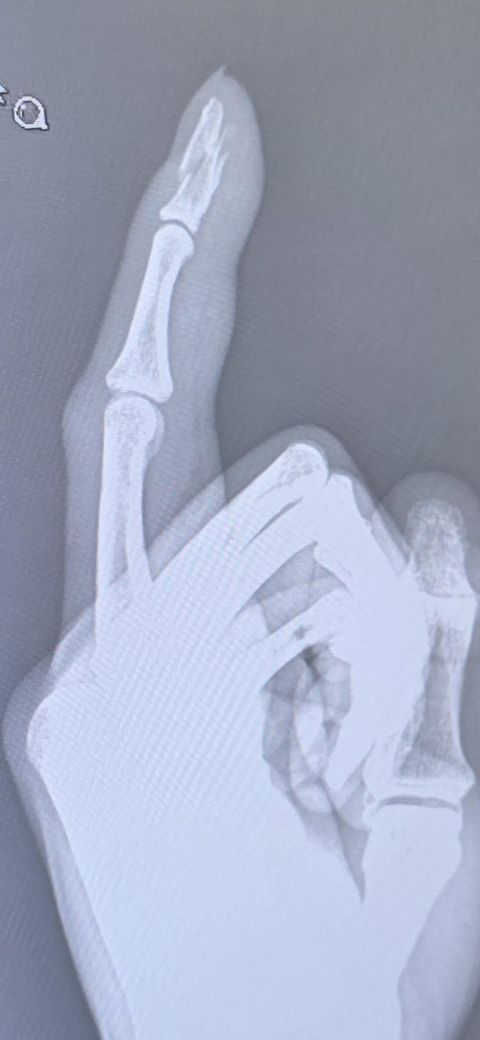

손가락 끝 분쇄골절입니다 비수술로 가능할까요?

손 끝 분쇄골절입니다.

이상태로 일단 부목만 한 상태 ( 반깁스) 이고

3일마다 엑스레이 찍어보고 이상태로 잘있으면 그냥 수술안합답니다

핀수술하기에는 뼈가 조각나있고 수술보단 깁스가 낫다고한데 손끝 뼈는 관절에 영향을 안줘서 괜찮다는데 일단 핀수술 보단 깁스치료가 더나을까요? 잘못붙는다고해서 휴유증 남을확률 있을까요?

• 1번 째 사진

• 2번 째 사진